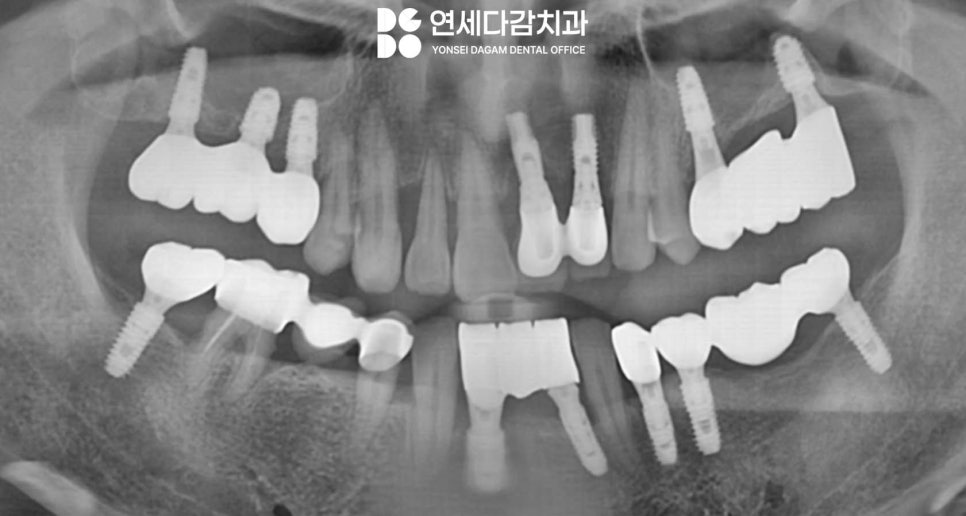

이 과정을 통해 수술 부위 모두

골 유착이 원활하게 진행되어

안정적인 결과를 얻을 수 있게 됩니다.

임플란트 치료는 개개인의

뼈 상태와 구강 환경,

그리고 적절한 제품 적용이

모두 어우러질 때

이상적인 결과를 얻을 수 있습니다.

임플란트가 자연치의

100% 대체는 아니지만,

기능 회복과

심미성을 제공할 수 있다는 점에서

치아 상실한 경우 중요한

치료 옵션임은 분명합니다.